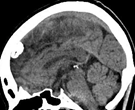

傍矢状静脈洞髄膜腫

上矢状静脈とは、頭の中央を走行する太い静脈です。その静脈の壁に接した硬膜から発生する髄膜腫は、無症状のこともありますが、腫瘍のサイズが大きいと手足の運動を司る場所(中心前回と言います)が圧迫を受けるために麻痺やけいれんを生じることがあります。

(術前MRI)

(術後MRI)

ところが、たとえ腫瘍が小さくても、下の画像に示すように、造影される病変(左)に比べ、脳浮腫(右;白く広がっている部分)が広い範囲に拡大していると、腫瘍の大きさが小さいにも関わらず症状(この場合右足の麻痺やてんかん発作)が重症化することが多いです。腫瘍摘出を行なうと、術後3~4週間で浮腫は消失します。